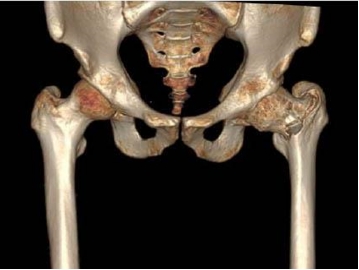

骨肉瘤是最常见的原发性恶性骨肿瘤,好发于10-25岁青少年。骨肉瘤增殖能力强、进展迅速、易发生早期转移,患者的预后较差。考虑到患者年轻,切除肿瘤的同时如何保证患肢的功能成为了问题的关键。诊断明确后,科室专家在胡勇主任医师的带领下为患者定制了新辅助化疗为保障的保肢治疗方案。化疗后达到了安全的外科边界,3D打印手术模型,精准切除肿瘤,定制截骨导板和3D打印的髋臼为患者量身定制3D打印全髋关节假体。

胡勇主任医师、徐生林副主任医师成功为患者实行了肿瘤全关节广泛切除3D打印定制髋关节假体置换术。该手术方案需要医工结合,技术难度高,但可将肿瘤切除彻底,肢体达到功能重建。